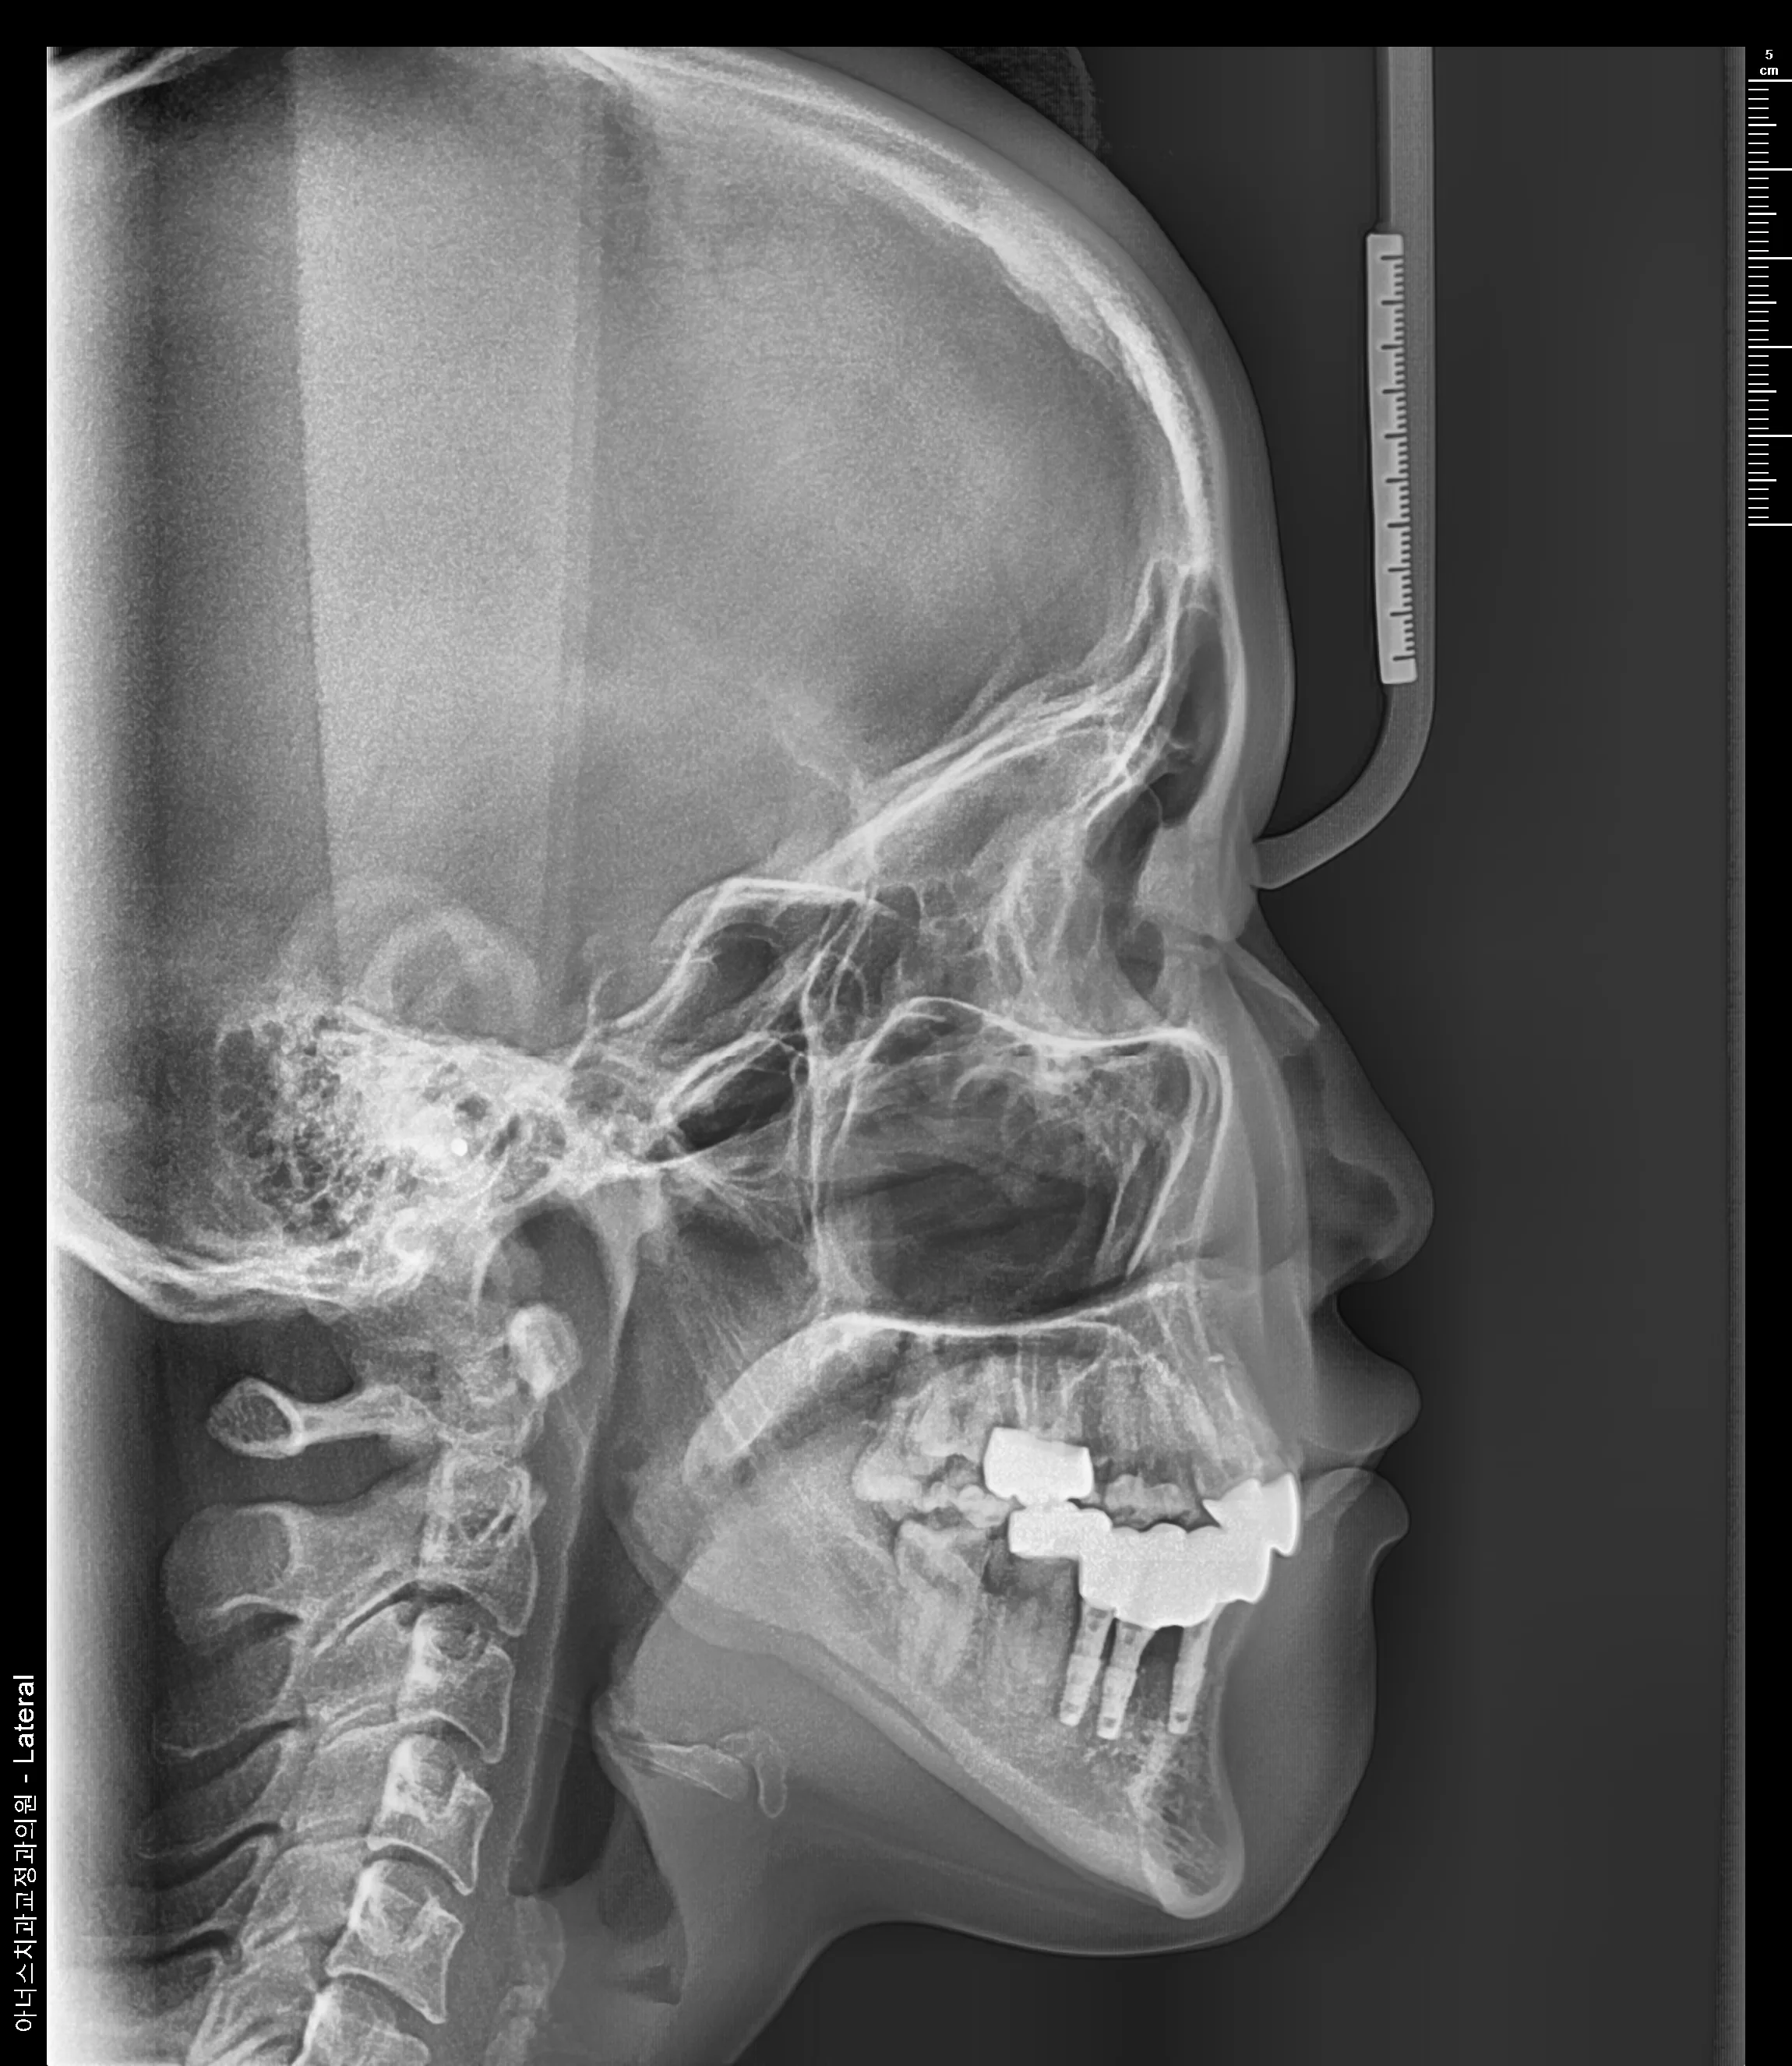

만 21세 환자로, 기존에 사고로 여러 치아를 다치고 상실한 상태로 매우 심한 교합무너짐이 있었습니다.

엑스레이

치료전 (Before)